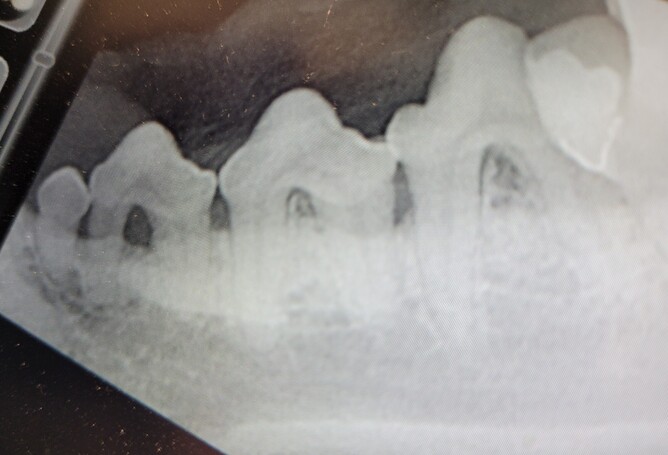

When it comes to dental health, what’s happening under your pet’s gums matters just as much as what you can see on the surface.

From the outside their teeth might look clean, white, and free from any obvious tartar or inflammation. But beneath the gum line can hide problems like infection, or even bone loss and furcation exposure – signs that periodontal disease is happening that would otherwise go undetected.

That’s where dental x-rays come in. They let our vets see what’s really going on – the roots, the jaw, and all the structures you simply can’t spot with the eye. It’s the same reason your own dentist takes x-rays: to catch issues early, before they turn into something painful later on.

In fact, studies show that x-rays can reveal hidden problems in up to 60% of pets whose teeth look normal on the surface. Without them, it’s easy for painful conditions to go unnoticed, leaving our furry friends at risk of chronic infection, discomfort and even tooth loss.

By including x-rays in every dental check, we can spot issues early, treat them properly, and keep your pet’s mouth healthy for years to come.